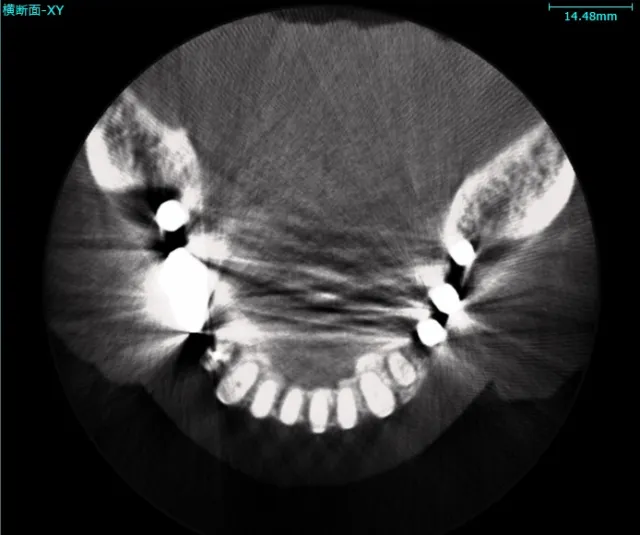

植入牙植入牙科填充物会导致伪影降低牙齿图像质量